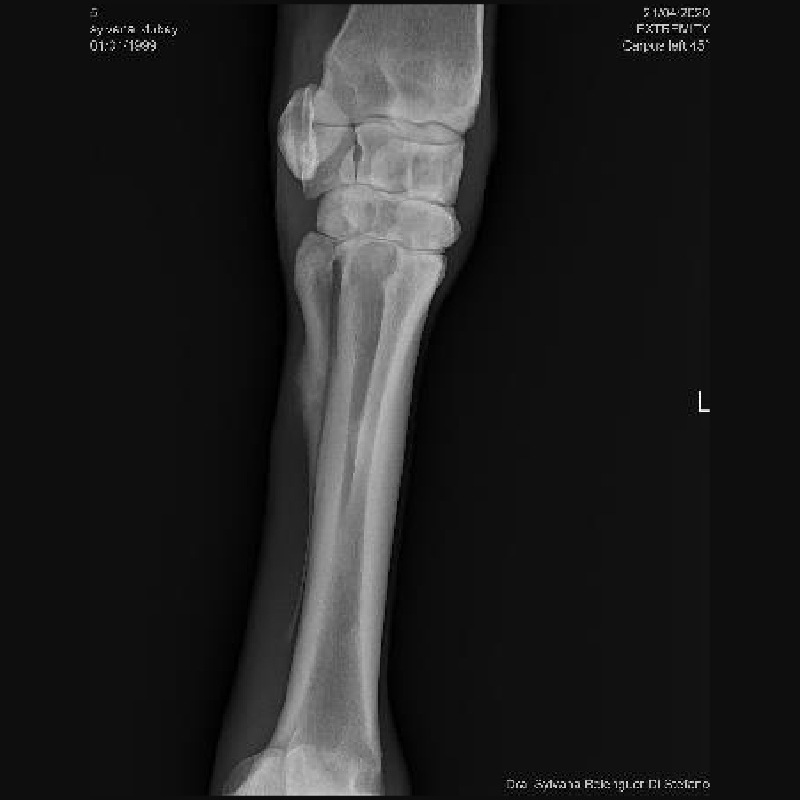

Tomosíntesis

EqueTom®

Tecnología híbrida entre RX digital y TAC, con 180–300 cortes por segundo y muy baja radiación.

• Detección de microfracturas y fisuras

• Visualización 3D parcial sin superposición

• Excelente sensibilidad para hueso cortical

• Solo requiere una proyección, reduciendo radiación.

• Bajo sedacion

Caso Dubay: La tomosíntesis permitió identificar fisuras múltiples no visibles en radiografía convencional, cambiando completamente el diagnóstico y el tratamiento recomendado.